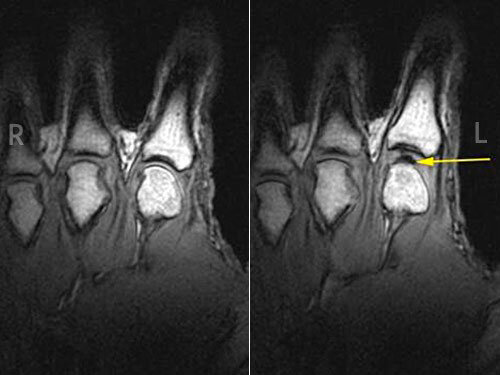

В первую очередь следует разобраться, почему хрустят пальцы. Дело в том, что все суставы наполнены синовиальной жидкостью – природной смазкой, довольно густой. Благодаря ей суставы меньше истираются и дольше служат человеку, не доставляя проблем. Если вытянуть палец, то объем сустава увеличится, а значит, давление в жидкости снизится. Газ, присутствующий повсюду, растворится и превратится в пузырьки. Через мгновение они лопнут с характерным хрустом. Этот звук многие люди принимают за хруст самих суставов.